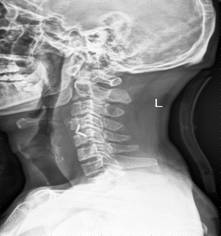

典型病例汇报1:中年男性41岁,因“行走不便2年,加重伴双手麻木2周”之主诉入院,症状主要为:颈部疼痛、僵硬,双下肢无力、行走不稳,双手麻木,协调性差,右手握笔困难。入院查体:步态不稳,C3-C7压痛、叩击痛,肢痛温觉减退,双上肢肢肌力5-级,双下肢肌力4-级,肌张力增高,双下肢腱反射亢进,病理征(+),行颈前路小切口突出椎间盘切除、前路颈椎桥形锁定植骨融合(ROI-C假体),无需前路钢板,术后四肢麻木明显缓解,右上肢精细动作明确增强,可写字,行走不稳消失,肌力基本正常,颈部活动度无明显受限。(1、图2)

图1 术前颈椎MRI提示颈椎退行性变,C4/5椎间盘突出、脊髓出现高信号改变,C4硬膜囊受压变形